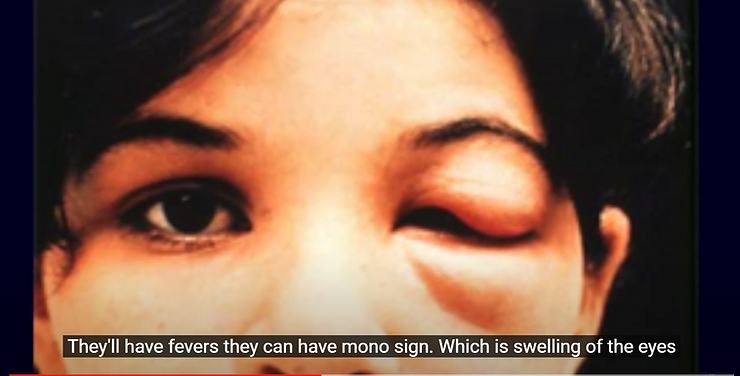

The vaXXXine induced Sudden Infant Death Syndrome is now joined by the Sudden Adult Death Syndrome and the medical authorities actively look the other way as hundreds of athletes drop dead on the playing field before the audience. And still, the vaccine has not been pulled from the market and the guilty prosecuted.

This includes dangerously low red blood cell counts, hemoglobin, hematocrit, white blood cell counts, including neutrophils, basophils, eosinophils, T and B lymphocytes all begin to drop below normal ranges because people are being poisoned by each toxic injection.